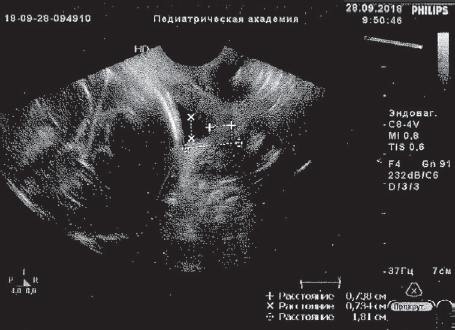

Получала сохраняющую беременность терапию с подключением трех сеансов мембранного плазмафереза (МПА) с возвратом гепаринкриомодифицированной аутоплазмы (при двух МПА по 200 мл), 12 сеансов ФК ультрафиолетовыми (№ 6) и лазерными (№ 6) лучами, без осложнений. После курса лечения анализы крови нормализовались, по данным УЗИ картина улучшилась, появилась сохранная часть шейки матки 6 мм, вероятно, за счет снижения внутриматочного давления в каудальном направлении. Пролабирования плодного пузыря за пределы наружного зева не визуализировалось в зеркалах и при УЗИ (рис. 1, 2).

Рис. 2. Данные ультразвукового исследования пациентки Ч., 33 недели беременности, после курса эфферентной терапии, динамика положительная

Fig. 2. Ultrasonic examination of patient Ch., 33 weeks of gestation, after efferent therapy course — positive results